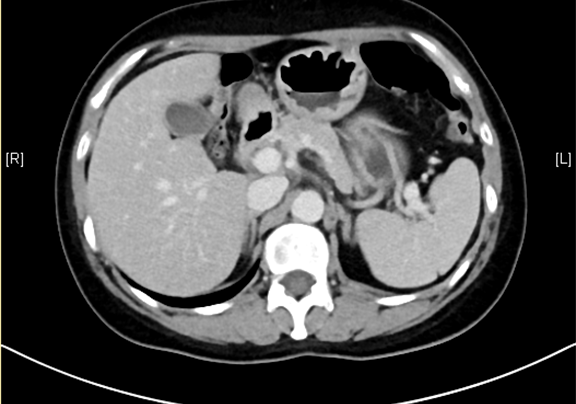

下腹部增强CT示:肝左外叶肝癌可能性大; 肝左内叶及右后叶海绵状血管瘤可能性大。

术前CT检查:

静脉期

平衡期

将0.625mm双源薄层CT资料的静脉期和动脉期Dicom格式文件导入海信CAS系统。

通过调节窗宽窗位调整CT序号,对肿瘤,肝实质,胆囊,下腔静脉,肿瘤,肝动脉、门静脉及肝静脉等进行三维重建;系统自动计算肿瘤体积和肝脏体积。